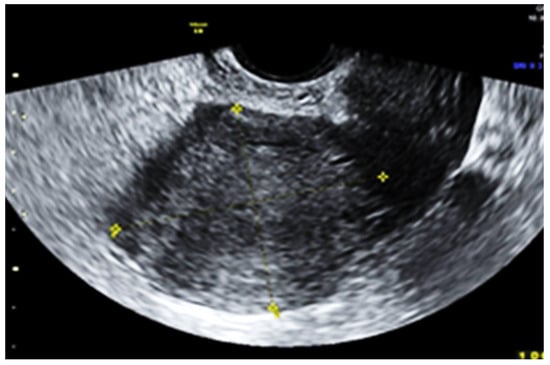

Subsequent ultrasound examination revealed a uterus with a homogeneous structure measuring 67/52/61 mm (Figure 1). However, in the lower portion of the uterine cavity and the upper part of the cervical canal, there was a non-homogeneous hyperechogenic mass measuring 72/30/75 mm (Figure 2). The mass exhibited numerous vessels (Figure 3), while the lower portion of the cervix appeared normal with a length of approximately 13 mm (Figure 4).

Figure 1.

The normal aspect of the uterine body.